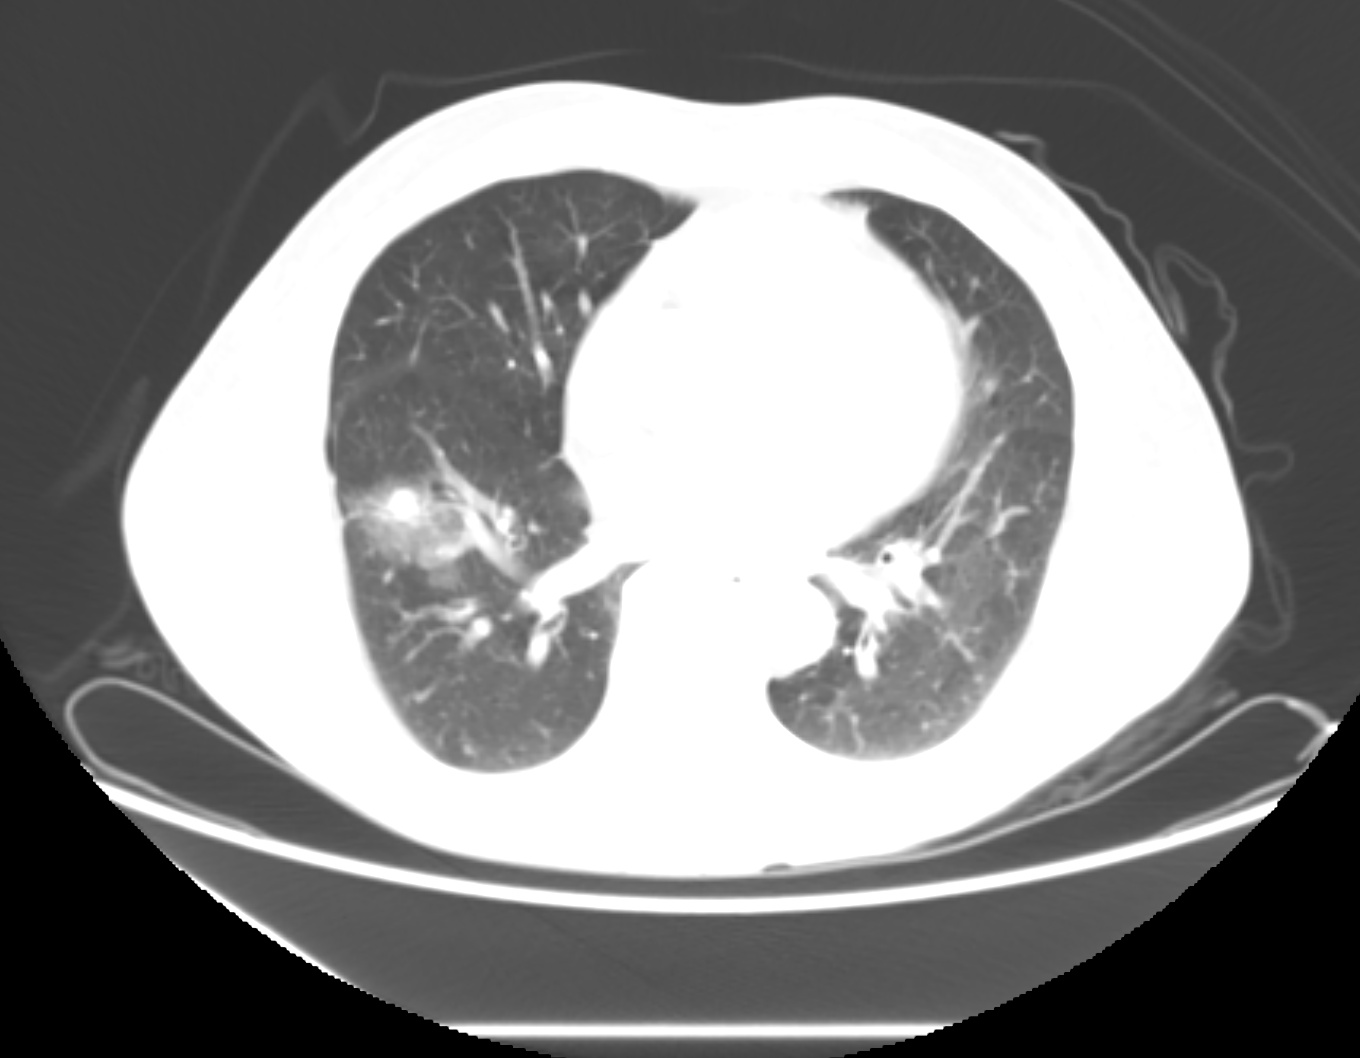

临床资料: 基本信息:女,63岁。现病史:咳嗽、咳痰1月余,胸闷6小时,增强CT显示右肺上叶后段:见肿块(95×76mm),密度不均,增强不均匀强化,与邻近血管分界欠清既往史:自身免疫性疾病“结缔组织病(硬皮病)”;高血压、高血脂20年。